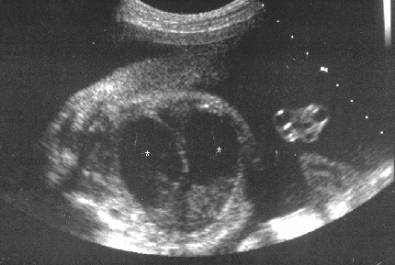

V- or U- shaped segments of bowel

Axial scans through the rectum can give the spurious impression that a presacral mass i.e. sacrococcygeal teratoma or anterior meningocele is present. The transducer needs to be rotated into an oblique position which will demonstrate the typical appearance of the rectosigmoid colon.